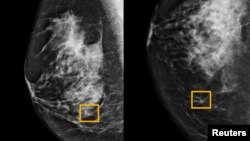

Quiz - Google System Could Improve Breast Cancer Detection